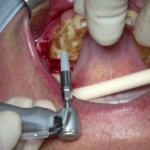

Rehabilitación completa maxilar (Full Arch)

Paciente: mujer, 59 años, edentulismo parcial.

Tratamiento: colocación de 6 implantes inmediatos con férulas apilables y prótesis provisional instantánea parcial.

Tiempo de intervención: 2 horas y 30 minutos.

Beneficios: intervención rápida y precisa, manejo conservador del tejido blando, estética y funcionalidad instantánea, alta satisfacción del paciente.

Estos casos ilustran cómo nuestro flujo BRDP y la cocreación clínica permiten resultados predecibles y eficientes, optimizando tanto el tiempo de sillón como la experiencia de paciente y clínica.